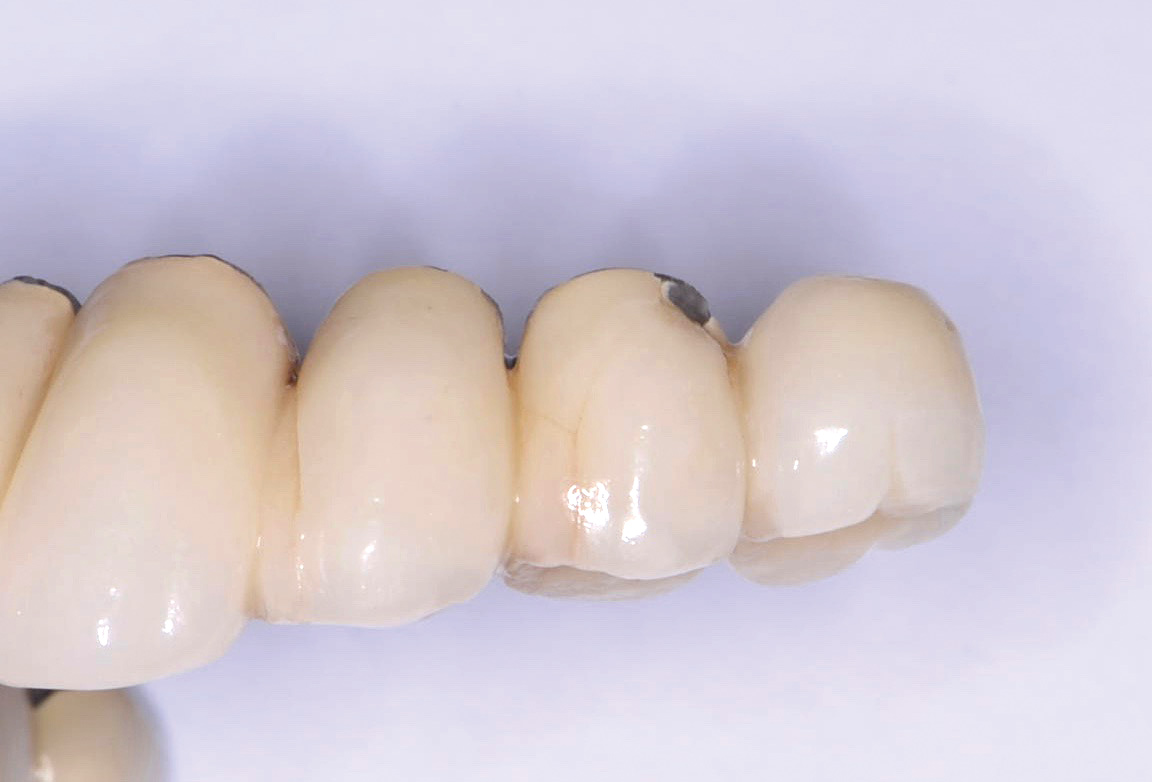

Fracture/Chipping of the Veneering Material

With 5-year complication rates from 3.2% to 25.5%,1 chipping of the veneering material (Figure 1) is the most common technical complication addressed in the literature.1,2 This can be minimized by designing the prosthesis before the final fabrication to ensure optimal framework design and thickness of the veneering material. Following basic occlusal principles in implant prosthodontics is essential. These include reduced cuspal inclination, narrow occlusal table, correction of load direction, reduced nonaxial loading, reduced length of the cantilever, and lighter occlusal contacts on implants.5 Restorations such as monolithic zirconia (Figure 2) and lithium disilicate are also being used to minimize chipping. However, long-term follow-up information on these restorations is limited.

Fig 1. Chipping of veneering porcelain of porcelain-fused-to-gold full-arch fixed dental

prosthesis.

Figure 1